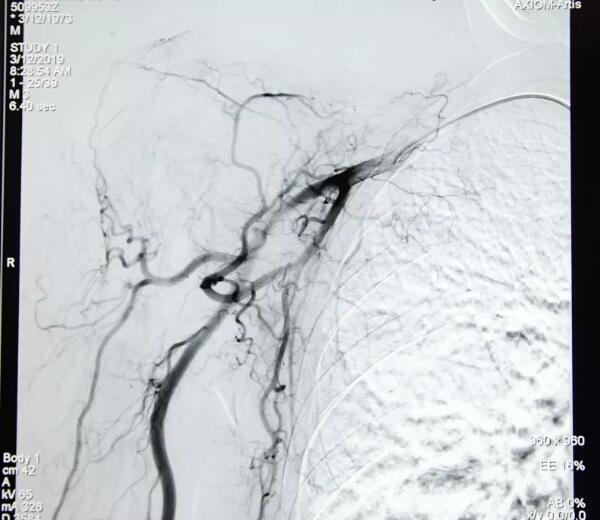

李先生于2018年在復大腫瘤醫(yī)院首先做了直腸腫塊穿刺活檢術,病理示:(直腸)低分化腺癌。于是他復查CT示“多發(fā)骨轉移瘤較前增多、范圍較前增大,胸7椎管較前稍變窄;雙側髂血管旁、腹股溝區(qū)及直腸周圍脂肪間隙淋巴結較前增大”。復大腫瘤醫(yī)院疼痛科副主任楊清峰及其他專家聯合診治后,因為他曾經在別的醫(yī)院有術后感染的情況,故決定先給予他介入治療消除他的疼痛感,因為介入治療具有很高的安全性和很低的風險性,可以降低術后感染的情況發(fā)生。

“患者已是直腸腺癌T4N2M1 Ⅳ期,姑息治療可以有效緩解他的疼痛” 介入治療的主治醫(yī)生楊清峰表示,“姑息治療也可以有所作為,不僅能夠改善病人的生存質量,還有助于延長生存時間。個別情況下,甚至能創(chuàng)造生命的奇跡”。

2019年經CT復查顯示李先生部分病灶縮小,患者四肢疼痛感明顯緩解,睡眠良好,生活可以自理了,“真是很神奇的,感覺就是睡了一覺,醒來后發(fā)現胳膊與腿都能自如活動了,我之前只能躺著,抬一下胳膊都會很痛”,經過介入治療后李先生這樣說。